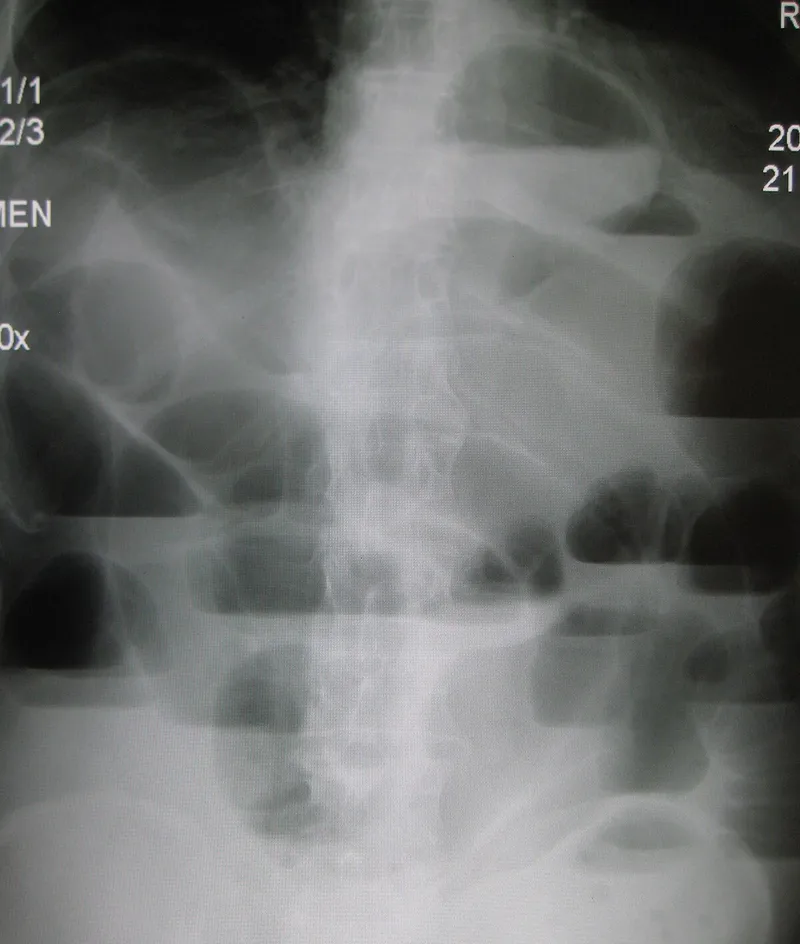

- X-ray (AXR): First step. Dilated bowel loops, multiple air-fluid levels, no distal gas.

- Signs: Double bubble (duodenal atresia), String of pearls (SBO).